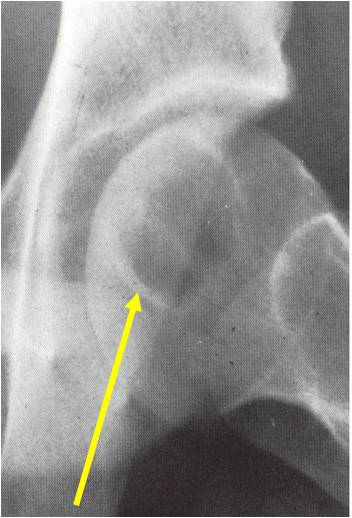

Radiographic Presentation

- Usually osteolytic, expansile lesion

- May be focally calcified

- Often a sharp interface between tumor and surrounding bone

- Sclerotic rim is uncommon

- Overlying cortex is usually thin, but intact